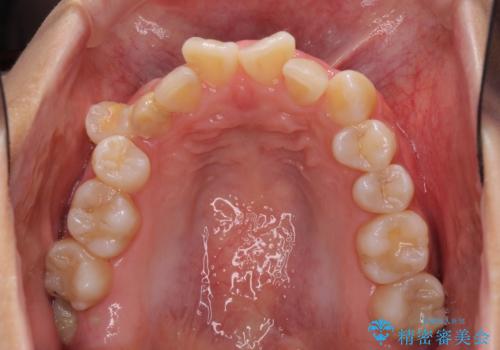

- 前歯のでこぼこと乳歯が残るほどの八重歯を気にして来院された患者様です。

非抜歯にてワイヤー矯正にて治療することとしました。(ただし、親知らずと乳歯は抜歯)

犬歯は歯根が太く長いため、移動には時間を要します。しかし、犬歯は機能面から考えて残すことを選択したいため、長期間をかけて治療を行うこととしました。

治療の度に歯列が改善していったため、長期間の治療も楽しく過ごしていいただき、満足のいく仕上がりとなりました。